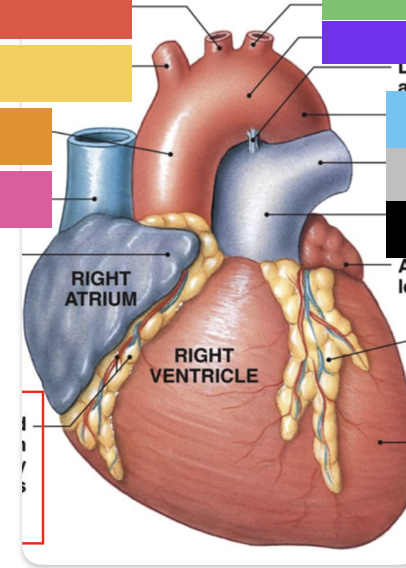

light purple

base

purple

apex

grey

right atrium

pink

right auricle

green

left atrium

green

left auricle

blue

right ventricle

orange

left ventricle

green

coronary (atrioventricular) sulcus

pink

interatrial septum

dark blue

interventricular septum

green

anterior interventricular sulcus

green

posterior interventricular sulcus

orange

aortic valve

yellow

pulmonary valve

red

tricuspid valve (right AV)

purple

bicuspid valve (left AV)

yellow

chordae tendineae

orange

papillary m.

blue

trabeculae carneae - only in ventricles

red

pectinate m. - only in R atrium

pink

fossa ovalis

grey

opening of coronary sinus

green

ligamentum arteriosum

green

fibrous pericardium

blue

parietal pericardium

pink

visceral pericardium (connective tissue) / epicardium (muscle)

purple

myocardium

grey

endocardium

pink

superior vena cava

black arrow

inferior vena cava

black

pulmonary trunk

red

right coronary artery

yellow

posterior interventricular artery

green

left coronary artery

blue

anterior interventricular artery

pink

circumflex artery

coronary sinus